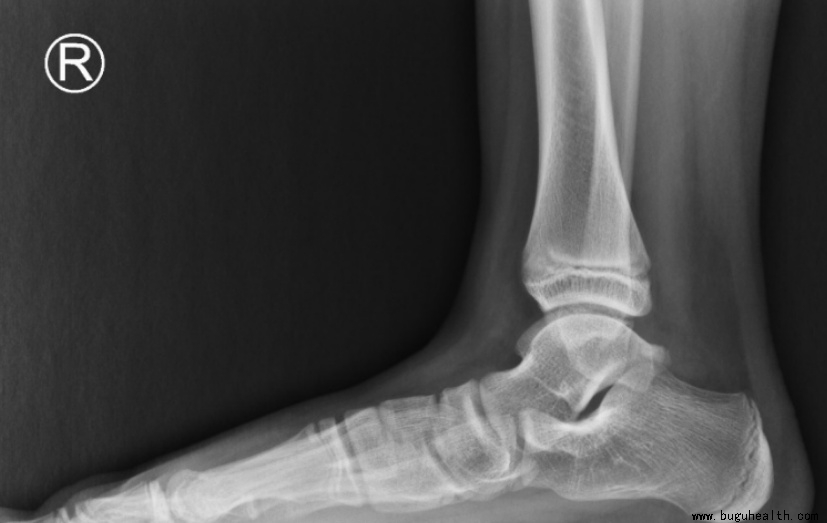

在医院医生常用的影像学检查为负重足部X线检查来评估足弓扁平、后足外翻和前足外展的情况,利用超声或MR来评估肌腱(胫骨后肌腱)和韧带病变(弹簧韧带和骨间韧带)情况。三维CT重建可以分析骨骼和关节形态,评估骨关节炎情况,并有助于制定截骨手术方案。

负重足部X线(侧位)提示足弓扁平